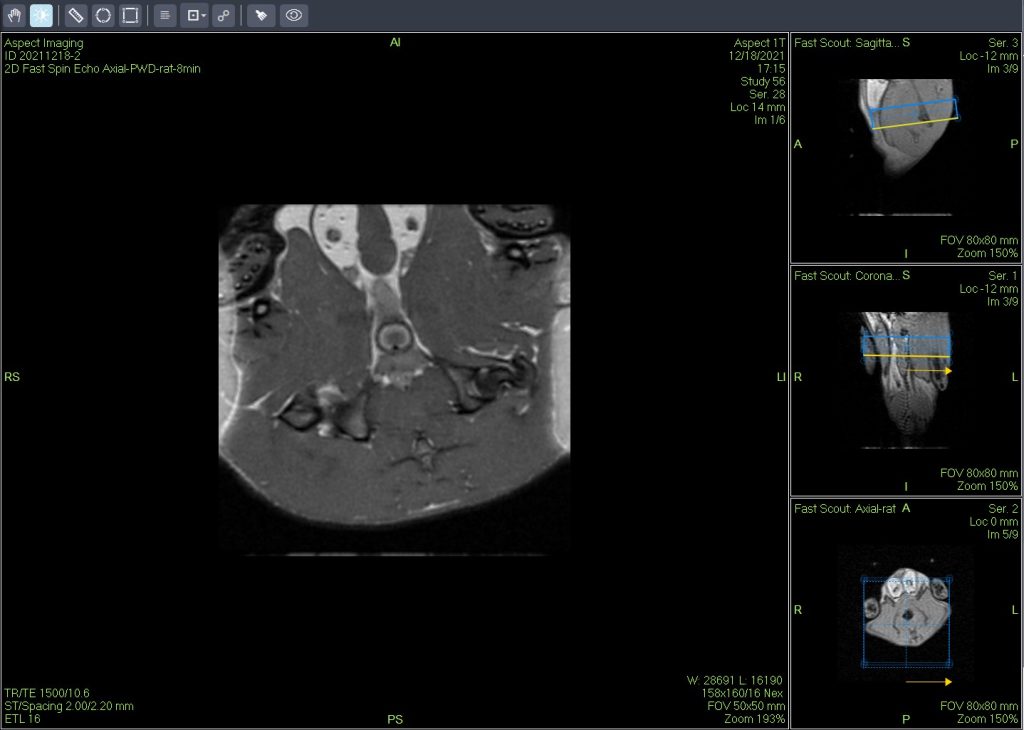

一個新的緊湊型高性能小動物磁共振成像平臺(M3),該系統使用一種新的磁鐵設計和一套相關的軟件,降低了小動物磁共振成像儀的成本和復雜性。這個新的MRI平臺為沒有磁共振或成像專業知識的病理學家提供了獲得活體實驗動物MRI和離體MRH高質量圖像的機會,從而可以大大增強臨床前毒理學研究和動物疾病模型開發中的常規組織病理學研究。

與超導小動物磁共振成像系統不同,緊湊型高性能小動物磁共振成像平臺是可移動式和自屏蔽的,因此M3可以放置在大多數實驗室或研究設施中,不需要特殊的屏蔽室、冷凍劑或冷卻劑,也不需要專用的電氣或管道供應。此外,緊湊型高性能小動物磁共振成像平臺具有專用的軟件和硬件以及預先編程的協議和樣本處理系統,以方便病理學家對活體動物或離體的動物樣本進行高通量成像。

緊湊型高性能小動物磁共振成像平臺的優點是能夠縱向監測疾?。ɑ铙wMRI)和快速獲取離體組織的多個切片(離體MRH),從而提供整個靶器官的三維數字形態學詳細數據,同時保持標本完整,以便后續常規組織病理學檢查。與傳統組織病理學提供的有限數量的二維(2-D)組織切片相比,核磁共振技術可以對毒理學效應和疾病進展進行更全面的評估。

活體磁共振成像在模型小鼠中檢測到局灶性肝損傷(圖A)。肝臟的高分辨率離體MRH評估可以在小鼠(圖B和C)中鑒定幾個單獨的局灶性脂肪病變。通過常規組織病理學證實病變為局灶性脂肪改變(圖C)。